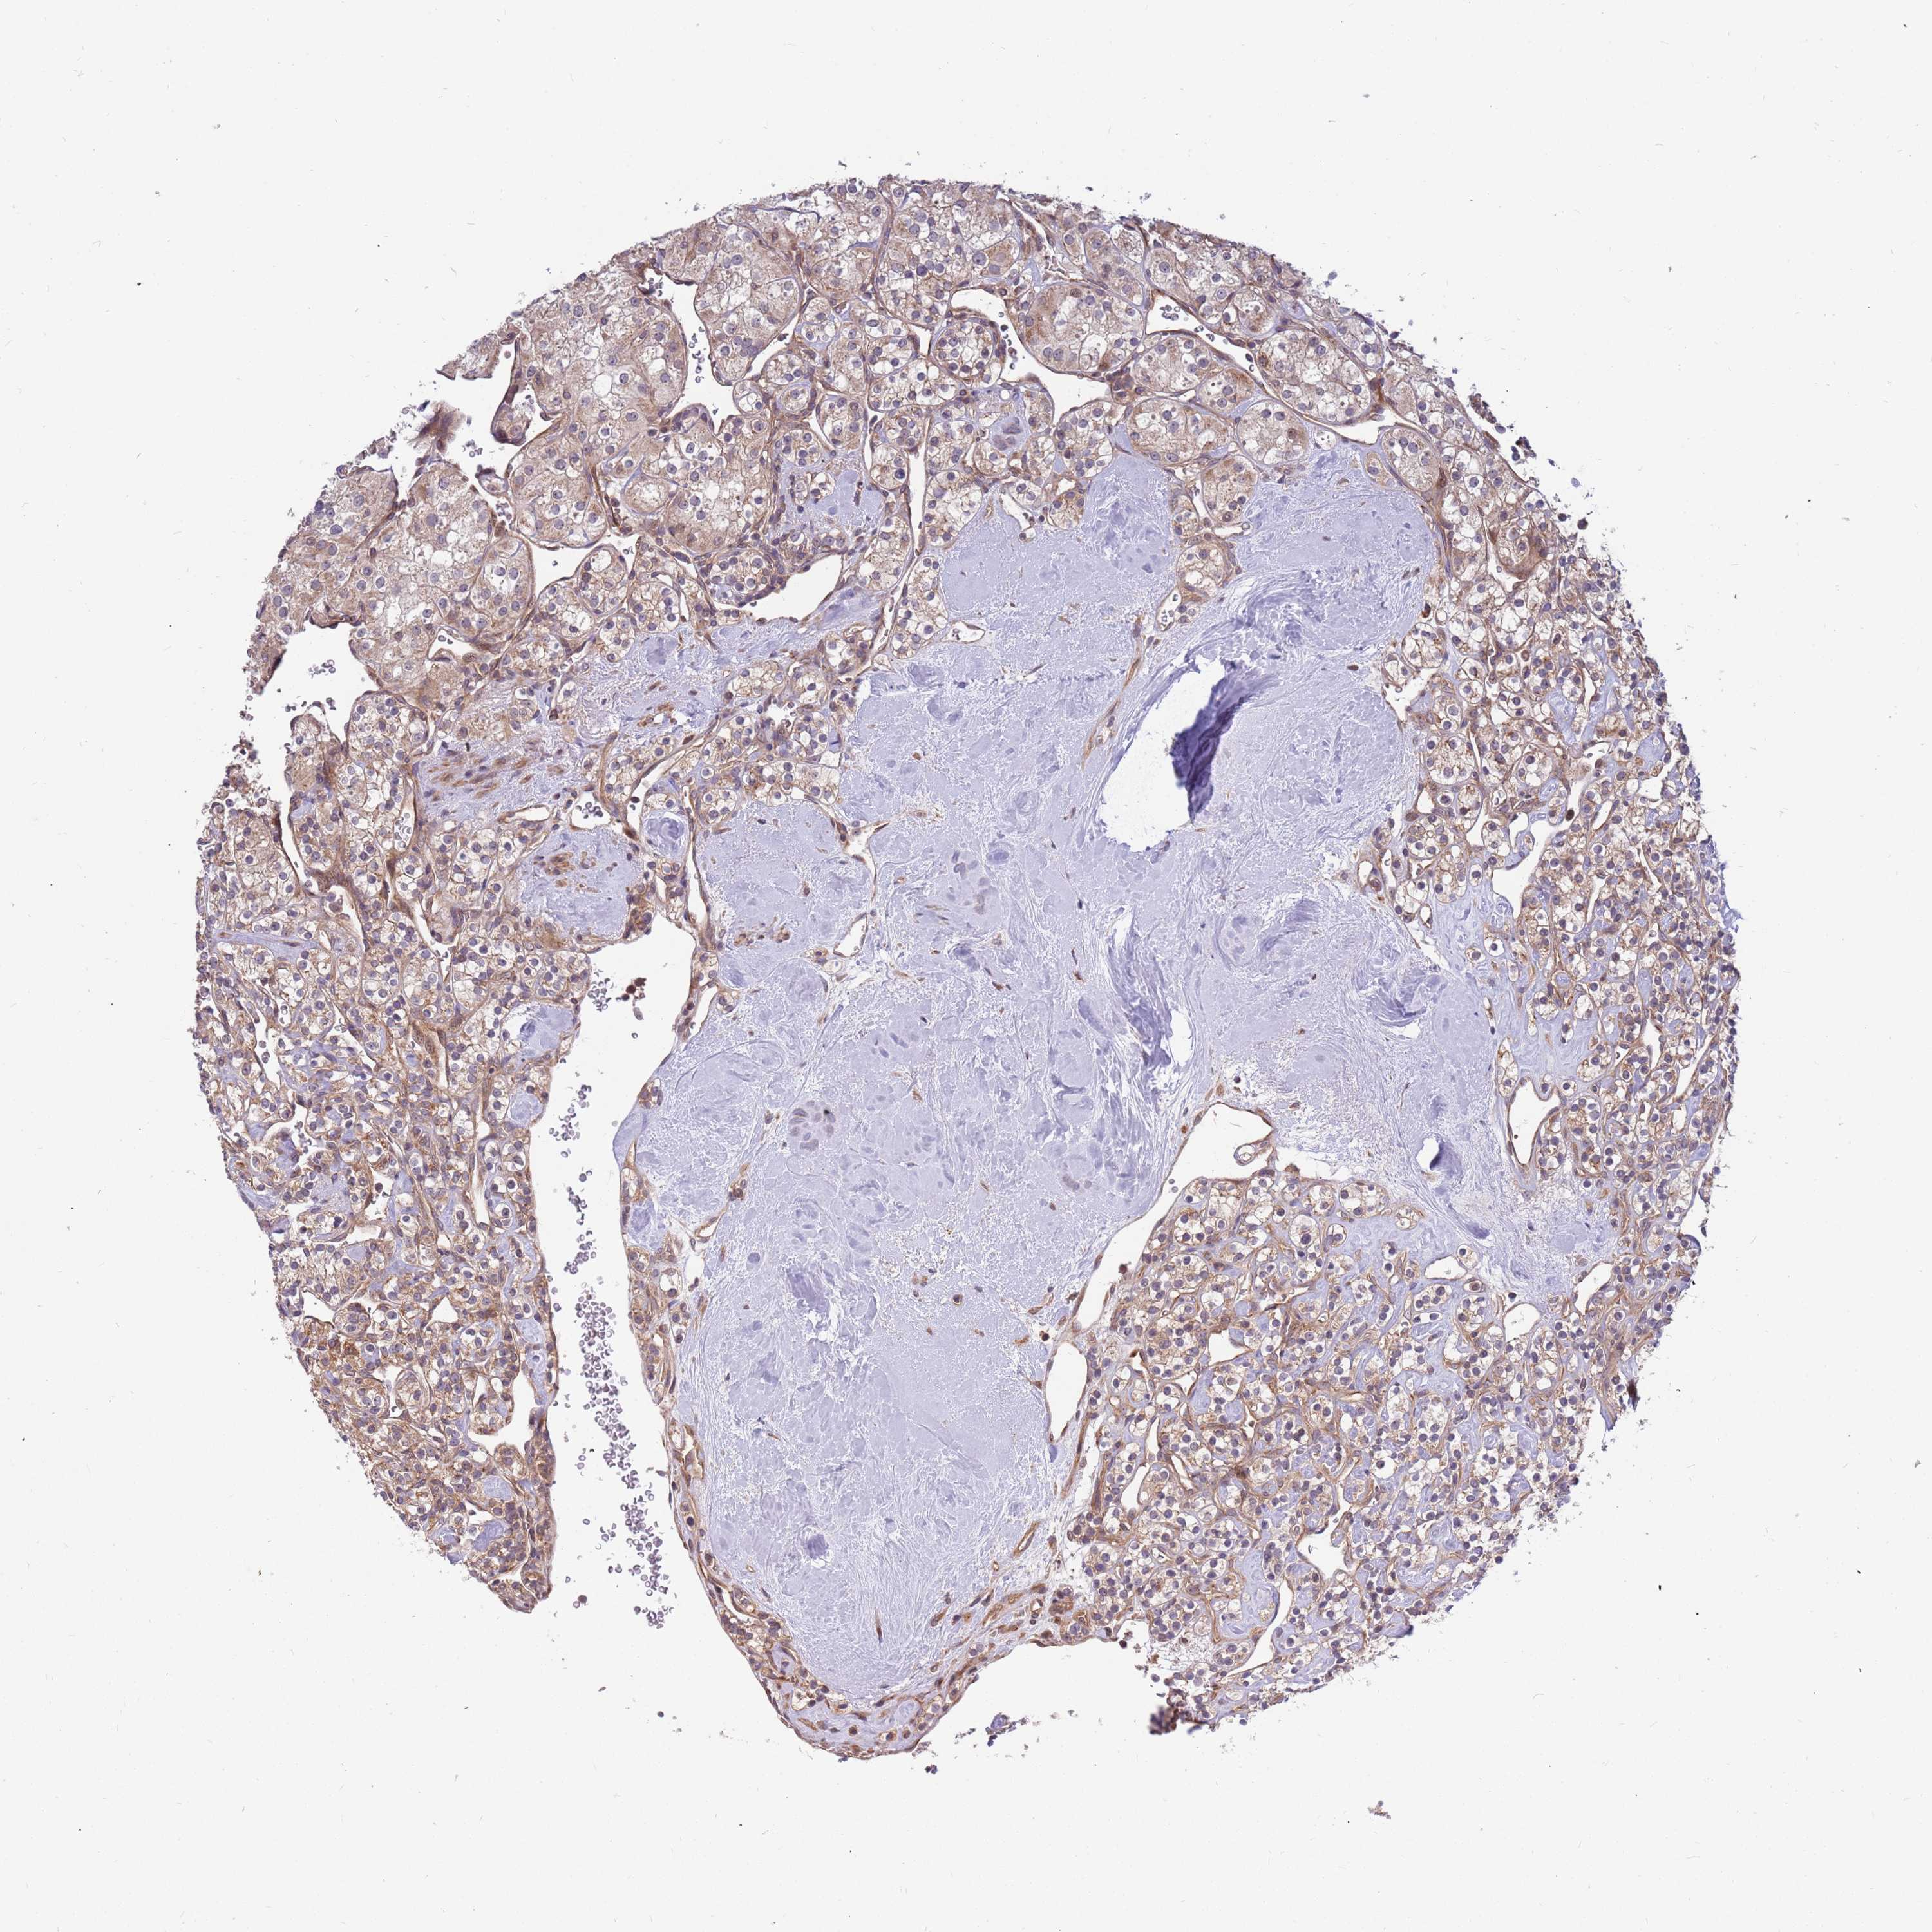

CANCER RENAL CANCER Show tissue menu

KICH TCGA KIRC TCGA KIRC VALIDATION KIRP TCGA PROTEIN RCC CPTAC PROTEIN EXPRESSION